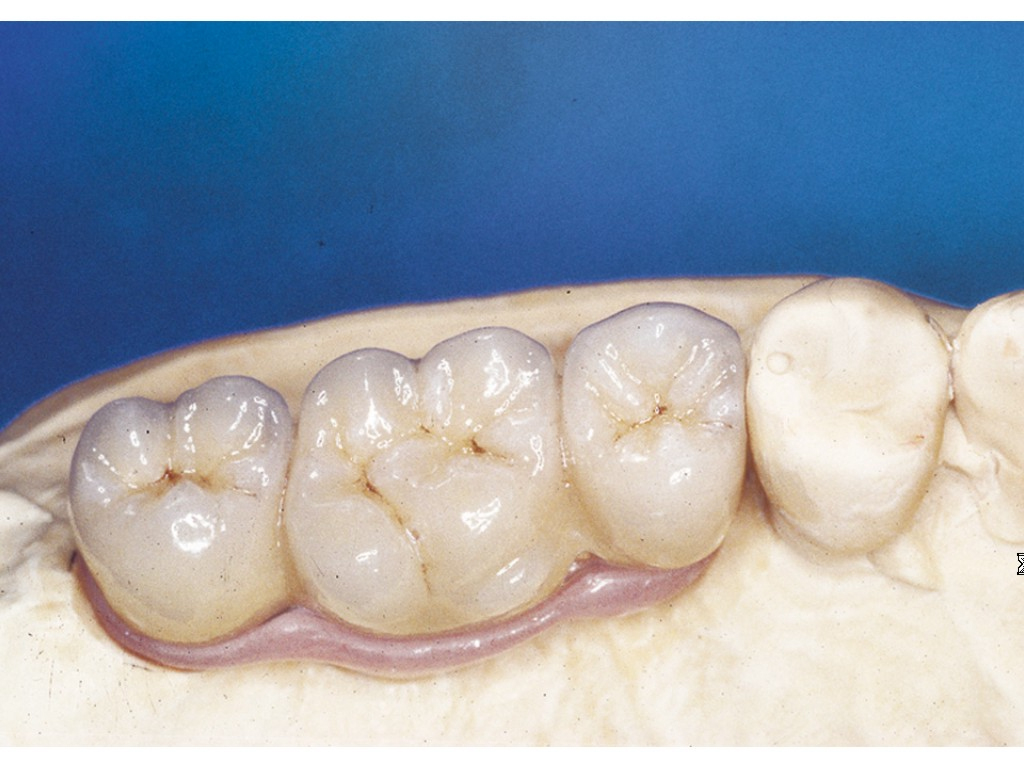

• Otisk situace v ústech a vytvoření modelu v laboratoři

• Zkouška zubní náhrady

Protetické řešení může být pomocí můstku, který je kotvený na implantátech nebo pomocí jednotlivých korunek na implantátech.

V zásadě je možné do těchto můstků zařadit i přirozené zuby, zejména pokud je potřeba tyto zuby ošetřit proteticky – korunkami. Korunky nebo můstky mohou být na implantáty nacementovány nebo přišroubovány.